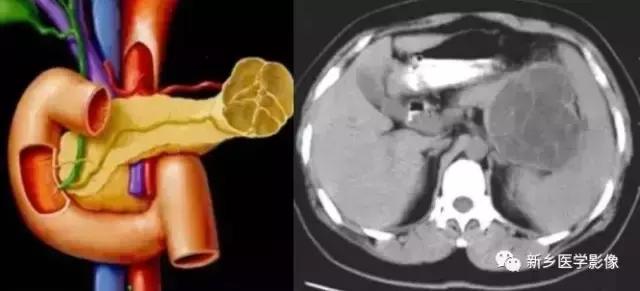

(一)浆液性囊腺瘤:

为最常见的胰腺囊性肿瘤, 良性, 不发生恶变, 至今也未见原发性胰腺浆液性囊腺癌的报道。好发年龄30 ~ 50 岁, 女性多见, 男女比例1 ∶6 ~ 1 ∶9 。一般无症状, 可有上腹部不适, 疼痛等, 有时可及肿块。浆液性囊腺瘤起源于胰腺中央的腺细胞, 根据囊的大小可分为三种类型, 即小囊型、大囊型和混合型, 其中以小囊型占绝大多数。